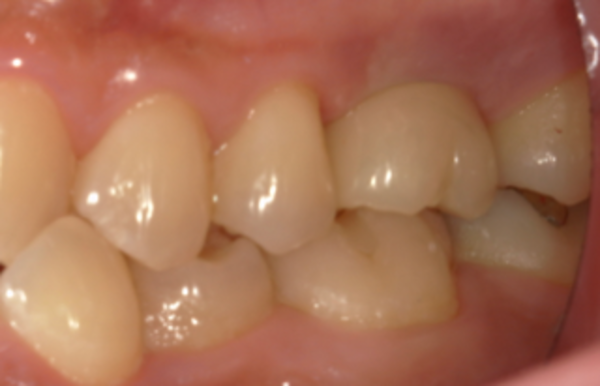

⑤ 被せ物の装着

インプラントの被せ物のジルコニアクラウンを調整し、口腔内のインプラントに装着しました。

があります。今回のケースではⅡを選択しました。

患者様は、抜歯が決まった際に不安が大きかったそうですが、インプラント治療後は左側でもしっかりと噛めるようになり、見た目も違和感がなく、大変満足されていました。